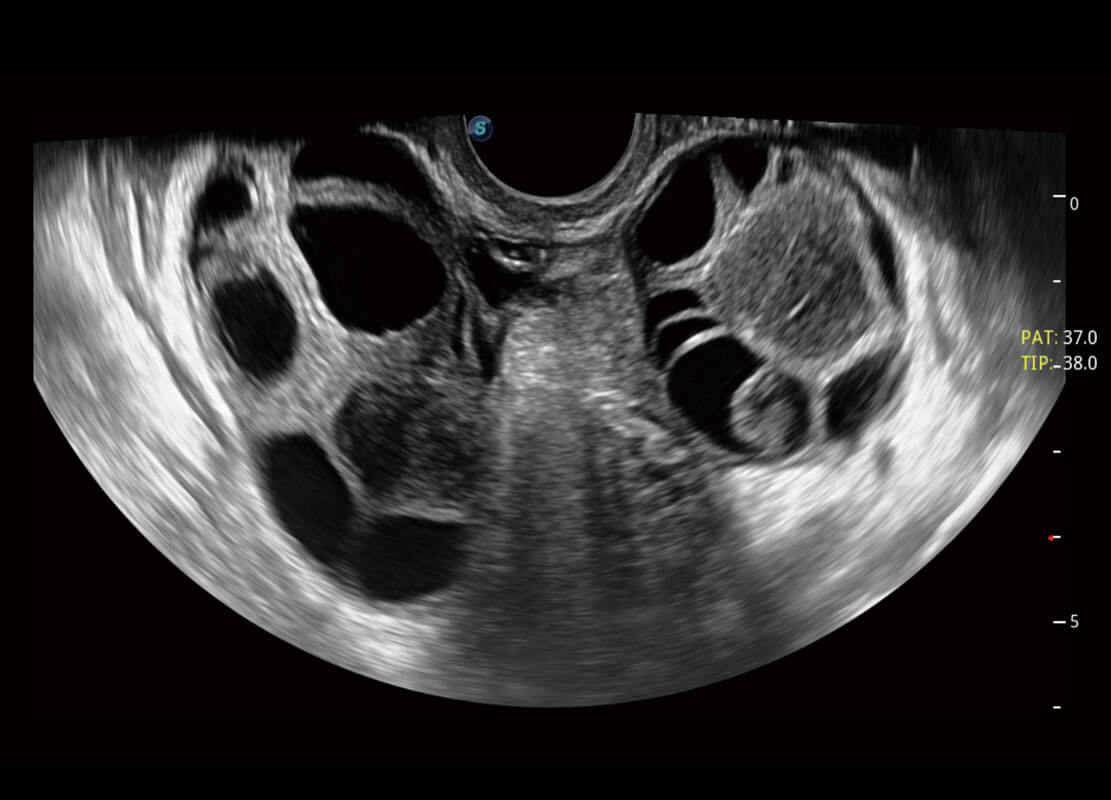

生殖健康

P60优异的图像质量搭载专科探头,在妇科基础疾病的诊断、卵泡生长的监测、输卵管通畅情况的判别等方面为您提供生殖应用方案。

• 腔内妇科-卵巢

• 腔内三维-宫内节育器

• 腔内三维-光影成像